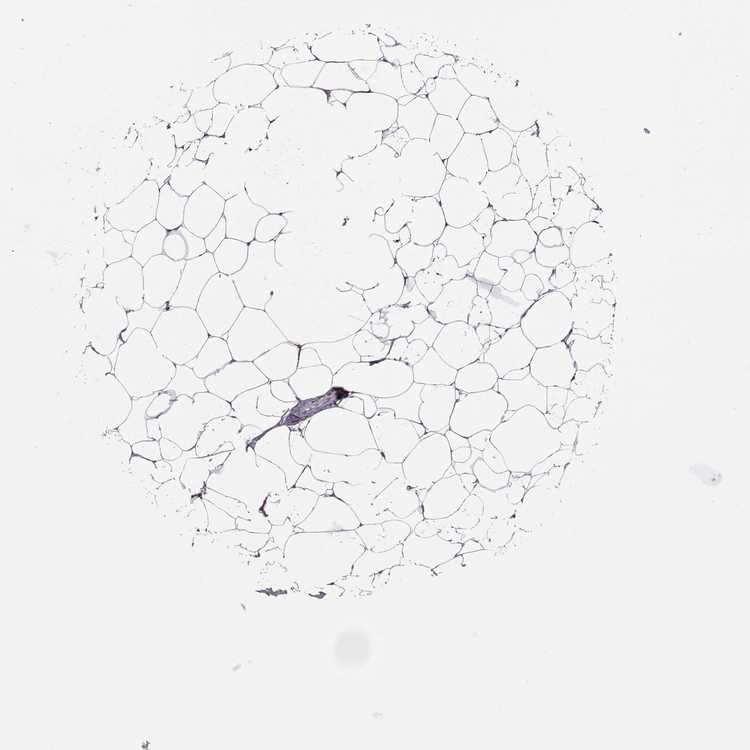

BREAST - Antibody stainingi

Antibody staining in the annotated cell types in the current human tissue is reported as not detected, low, medium, or high, based on conventional immunohistochemistry profiling in selected tissues. This score is based on the combination of the staining intensity and fraction of stained cells.

Each image is clickable and will lead to virtual microscopy that enables deeper exploration of all samples and also displays staining intensity scores, fraction scores and subcellular localization as well as patient and tissue information for each sample.

Antibody HPA064576

Adipocytes Not detected

Glandular cells Not detected

Myoepithelial cells Not detected